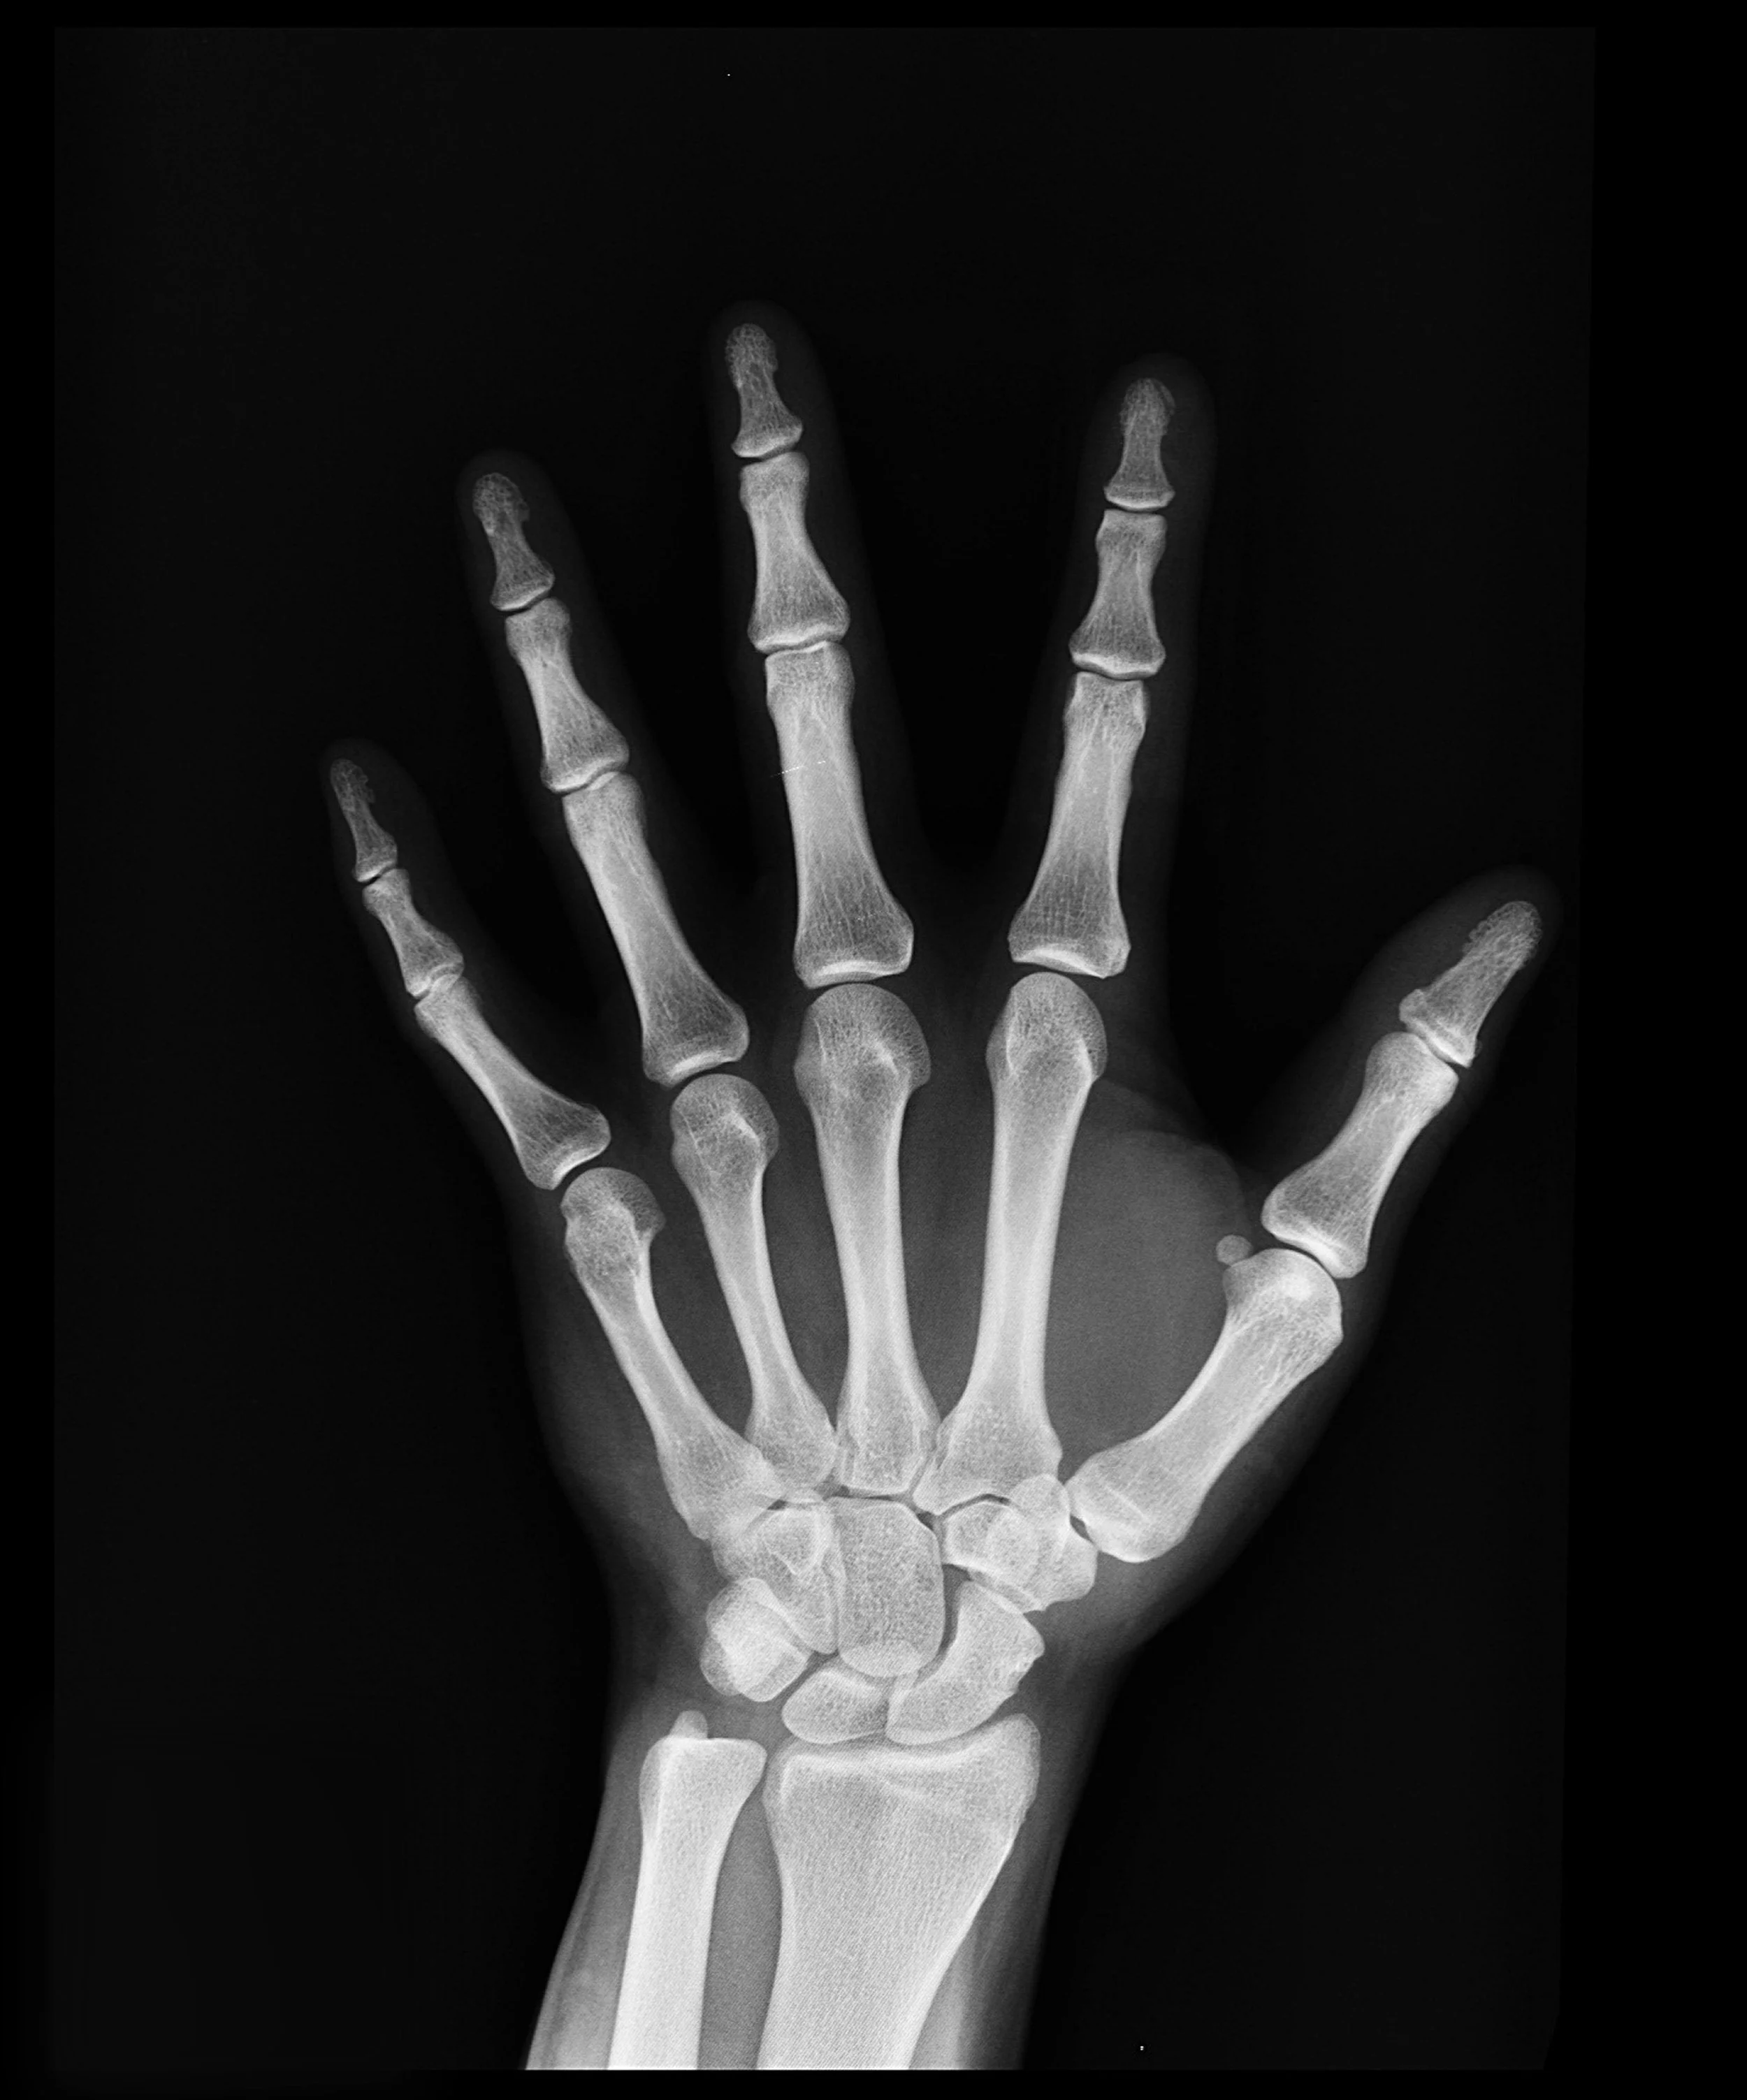

The hand’s complex anatomy consists of 27 bones, 27 joints, 34 muscles, over 100 ligaments and tendons, numerous blood vessels, nerves, and soft tissue.

The wrist is comprised of 8 bones called carpal bones. These wrist bones connect to 5 metacarpal bones that form the palm of the hand. Each metacarpal bone connects to one finger or a thumb at a joint called the metacarpophalangeal joint, or MCP joint. This joint is commonly referred to as the knuckle joint.

The bones in our fingers and thumb are called phalanges. Each finger has 3 phalanges separated by two joints. The first joint, closest to the knuckle joint, is the proximal interphalangeal joint or PIP joint. The second joint nearer the end of the finger is called the distal interphalangeal joint, or DIP joint. The thumb in the human body only has 2 phalanges and one interphalangeal joint.